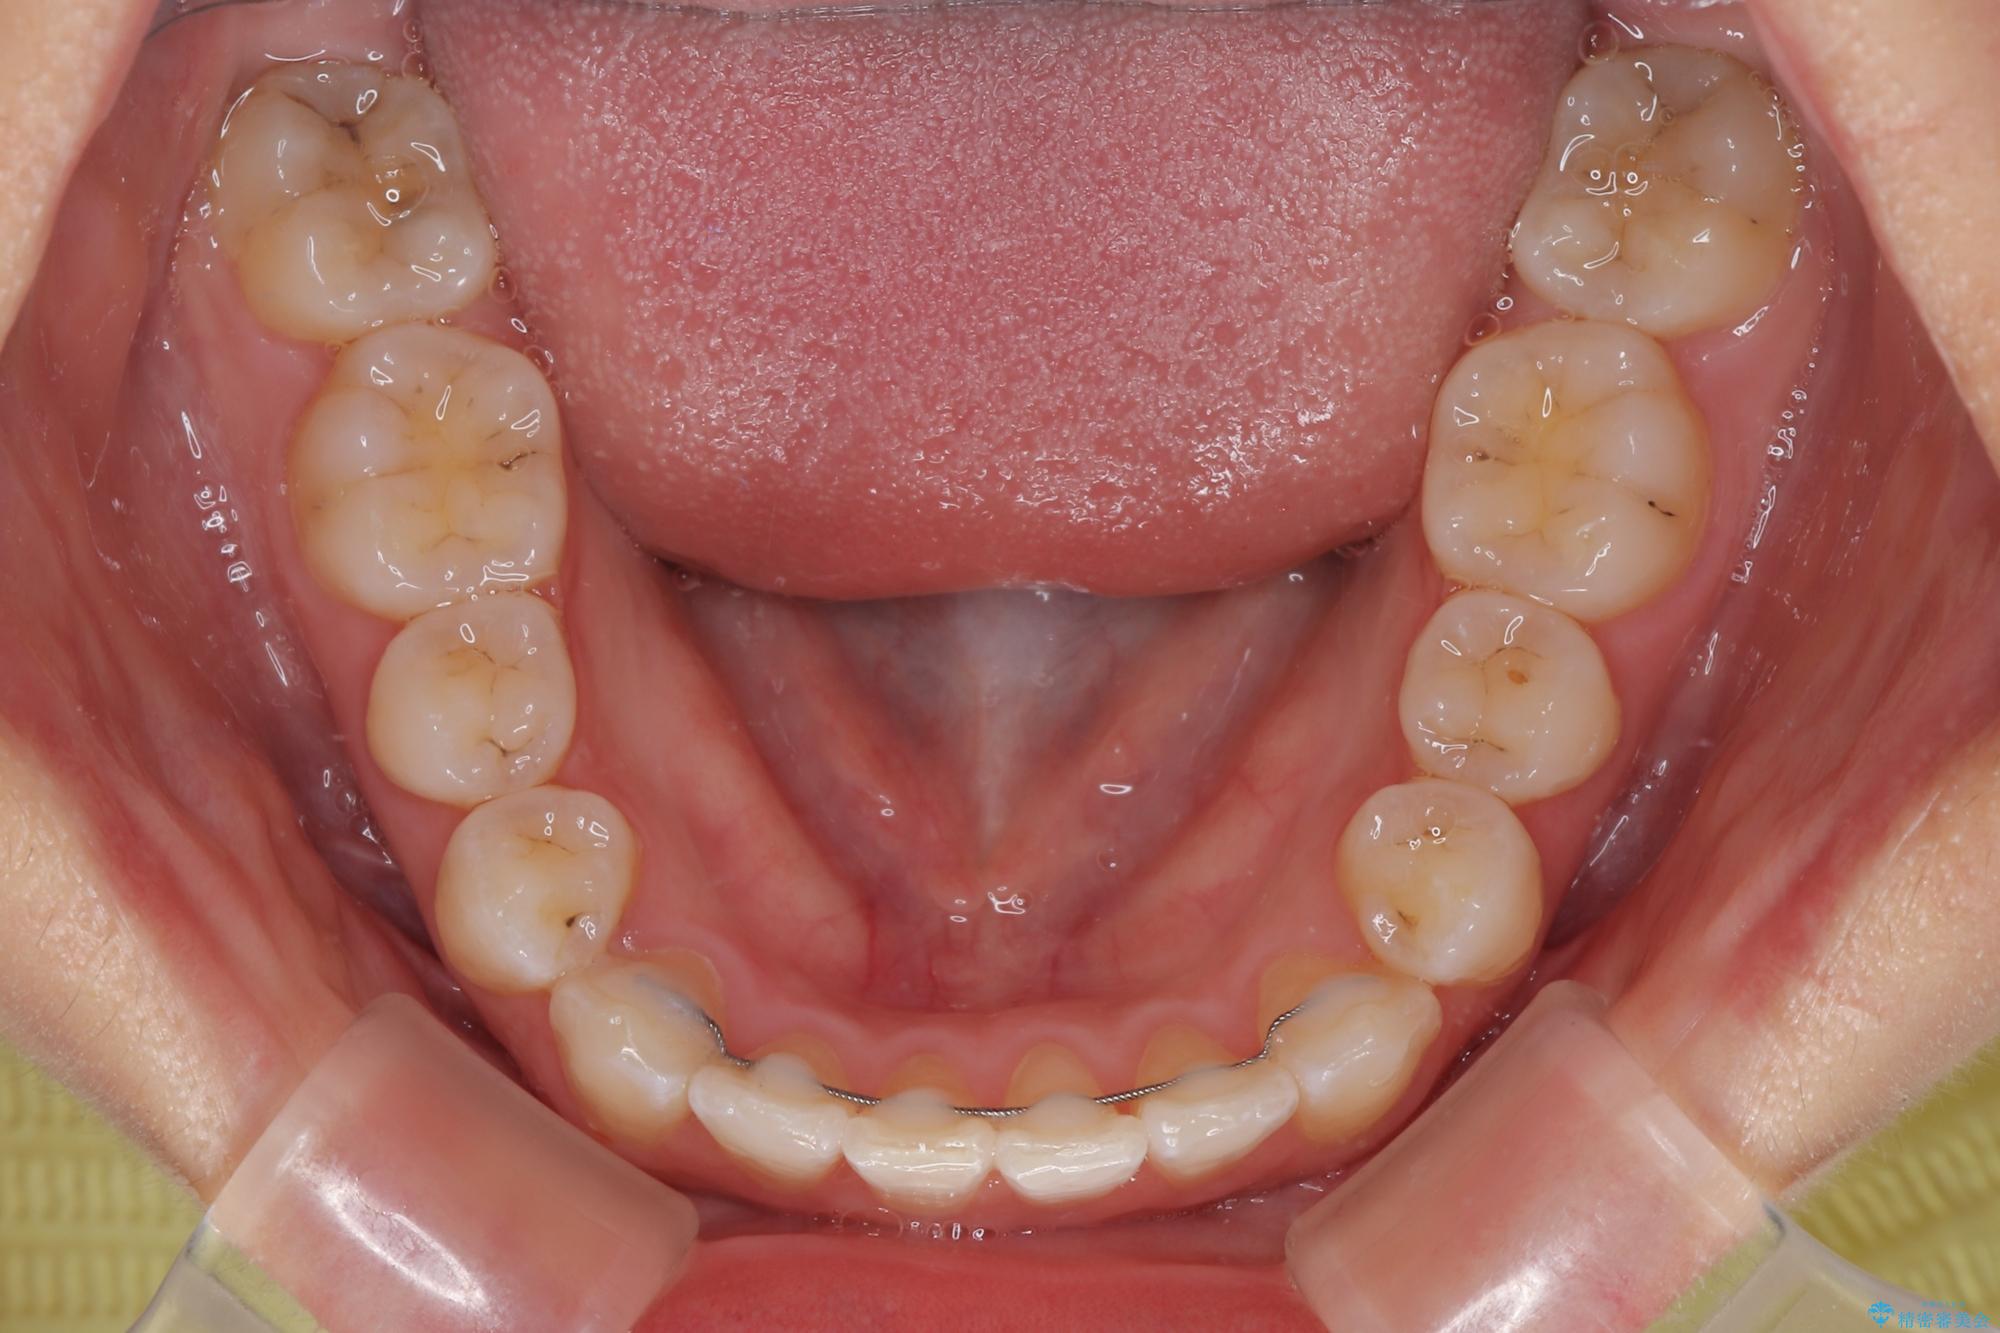

- 上顎前歯のクロスバイトを気にして来院された患者様です。

装置の外見を気にしていましたが、短期間で治療を終えることができるだろうと伝えると、安価であるメタルブラケットを選択されました。

想定通り、1年強で綺麗に仕上げることができました。